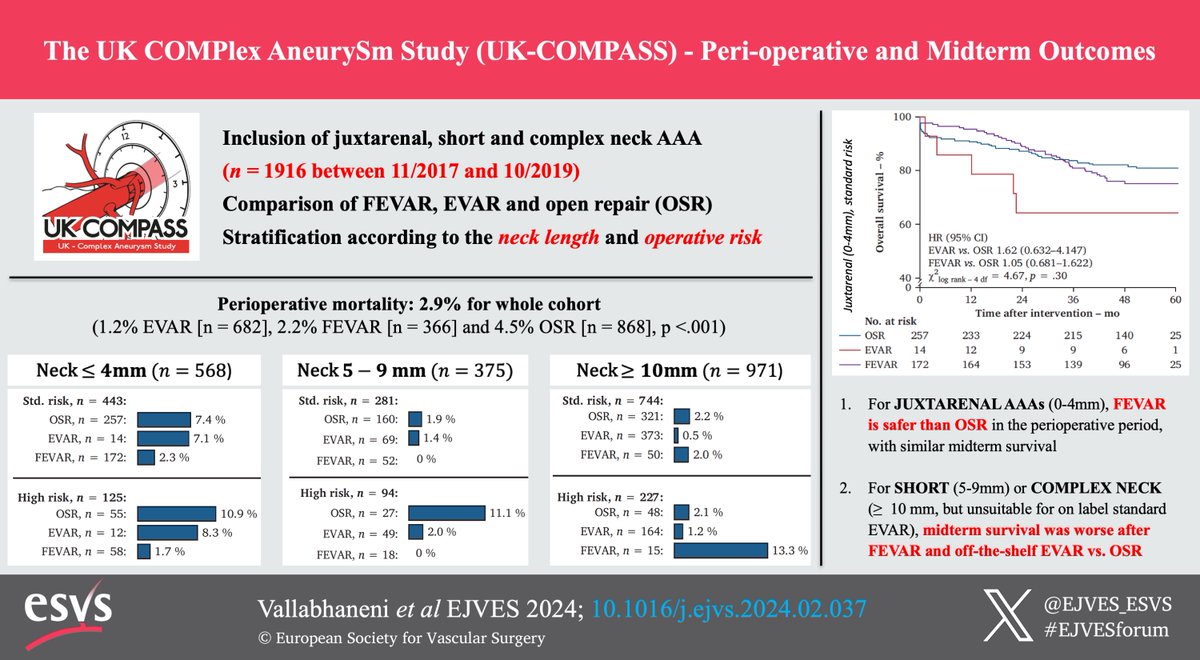

Don't miss this #EJVESVA of the 'UK- COMPASS Study: Perioperative and Midterm Outcomes' UK-COMPASS S R Vallabhaneni Jonathan Boyle @JoseeRijn Petar Zlatanović #aortaed doi.org/10.1016/j.ejvs…